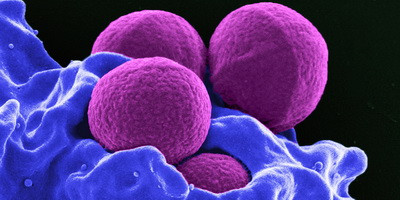

Віруси бактерій полегшили в мишей і кролів симптоми отруєння токсинами кишкової палички, тоді як лікування антибіотиками часто погіршує стан. Такого результату вдалося досягти завдяки тому, що всередину вірусів помістили інструмент CRISPR-Cas12, який вирізав ділянку геному, відповідальну за вироблення токсину. Хоча підхід ще потребує випробування на людях і визначення безпечної дози, він може стати методом прицільної боротьби з різними стійкими до антибіотиків бактеріями, не лише кишковою паличкою.